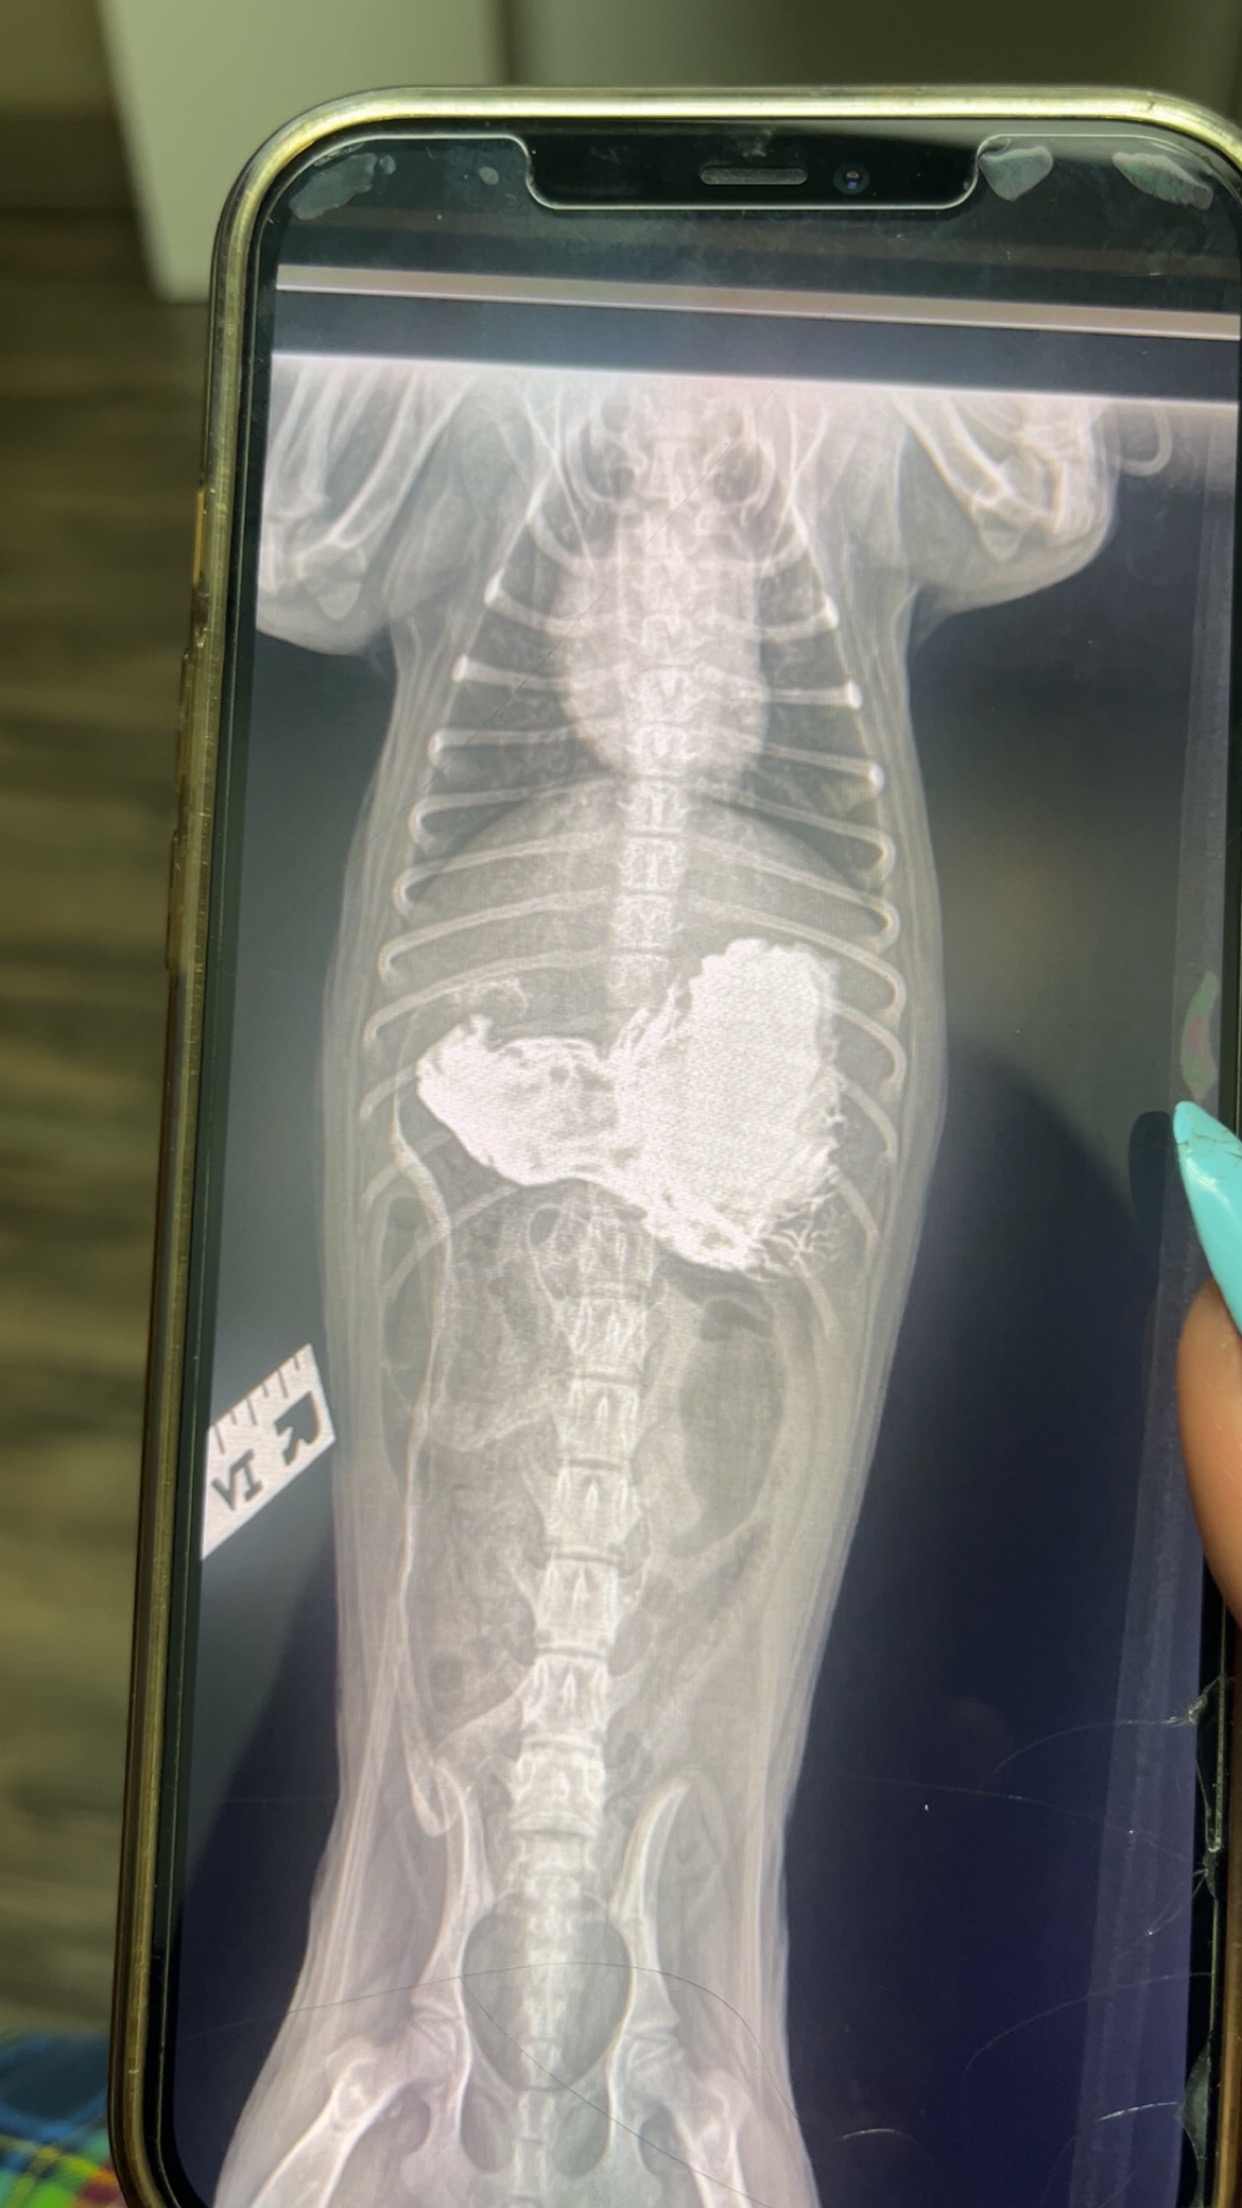

A few days ago, Theo swallowed something that caused a severe intestinal blockage. He’s been throwing up, refusing food, and crying in pain. The vet told us that he needs emergency surgery immediately — or he won’t survive.